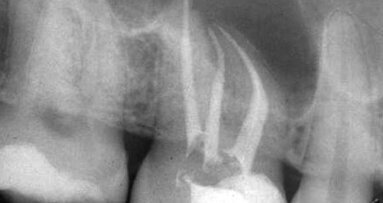

During the 1990s, computer technology gradually replaced hard copy paper records for patients, and scheduling became a more routine process. The influence of computers in the advancement of endodontics was incredible! Many in our profession today don’t remember the “darkroom,” the small, closet-like room in our offices where the developing and fixing of radiograph films was done. One of the most profound changes in dental technology was the advent of digital radiography. Cone-beam computed tomography (CBCT) became a huge asset for a better diagnosis, easier treatment and more predictable results. MTA was introduced as a new root-end filling material and to be used for perforation repairs.